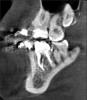

Oleg-Gru Опубликовано 8 апреля, 2013 Поделиться Опубликовано 8 апреля, 2013 (изменено) Здравствуйте! Полтора года назад был пролечен 36 зуб, закрыта старая перфорация коронковой части, пройдены каналы, сверху накрыто МК. На данный момент видимого ухудшения состояния этого зуба нет. Месяц назад, по ортодонтическим причинам, было сделано КТ. Интересует текущее состояние шестерки.Как вы думаете, каков ресурс у этого зуба? Пару-тройку лет протянет? Заранее благодарен! Изменено 8 апреля, 2013 пользователем Oleg-Gru Ссылка на комментарий

DmitrySH Опубликовано 9 апреля, 2013 Поделиться Опубликовано 9 апреля, 2013 Зачем прицельный снимок? КТ не очень хорошее. Пломбировочный материал сильно фонит и портит картину. Ссылка на комментарий

IvanK Опубликовано 10 апреля, 2013 Поделиться Опубликовано 10 апреля, 2013 КТ не очень хорошее. Пломбировочный материал сильно фонит и портит картину.думаю, что "покрутив" в реальном времени все будет ясно Ссылка на комментарий